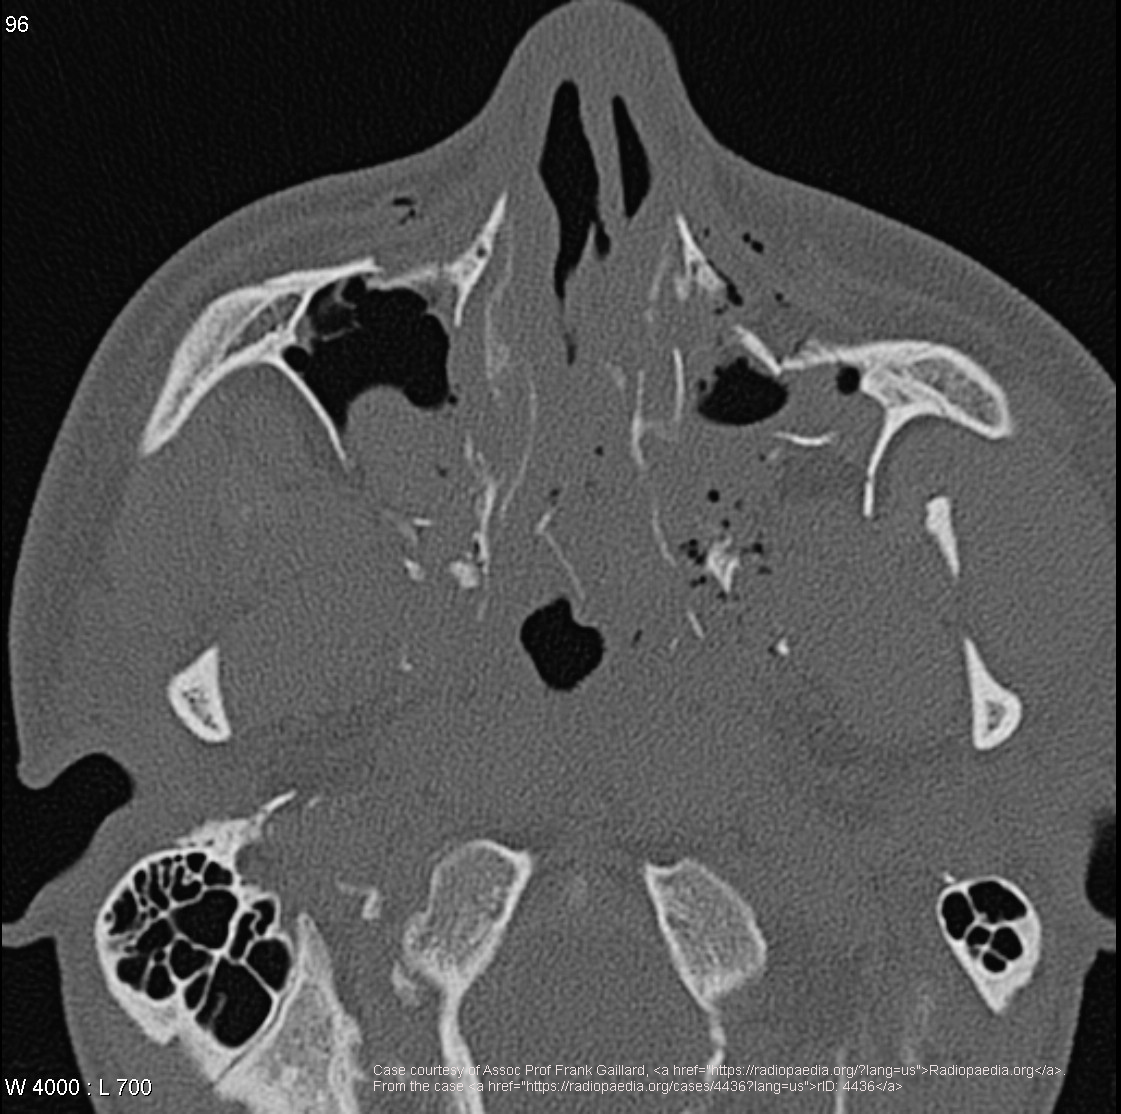

What is a common sign of an inferior orbital rim blow-out fracture?

Tear-drop opacity from trapped orbital muscles.

What is a possible complication of maxilla fracture affecting vision?

Restricted upward eye motion from optic nerve entrapment.

What is the typical cause of a zygomatic arch fracture?

Direct trauma.

Name one functional complication of a zygomatic arch fracture.

Lacrimal obstruction.

Which sites are involved in a tripod fracture?

Zygomatic arch, orbital floor/rim, and zygomatic-frontal suture.